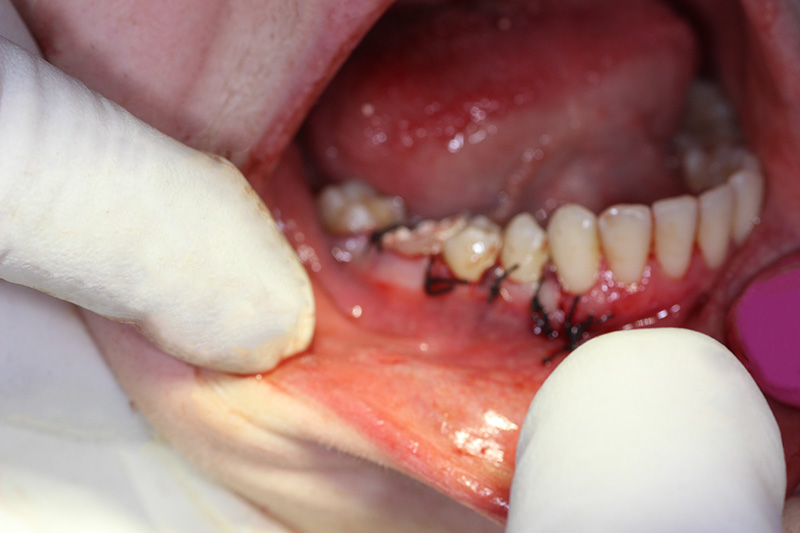

The patient underwent an operation of apicotomy (resection of the apex of the tooth root) and removed the cyst.